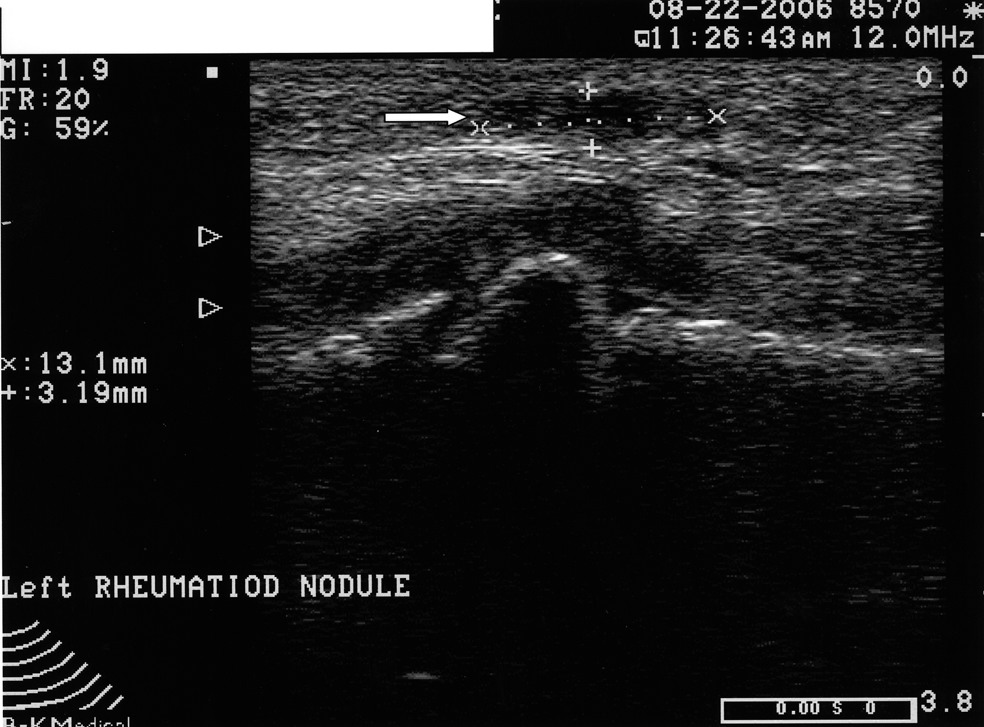

Podiatrists are the experts in dealing with pathology of the heel. It remains one of the leading pathologies that we see clinically. It is also an anatomic area that is easy to ultrasound. While it has been one of the first areas that clinicians new to ultrasound use the device for, I believe this modality is underutilized overall. Granted, podiatrists can diagnose plantar fasciosis clinically with a high degree of accuracy without the aid of ultrasound. However, there are other causes of heel pain that can mimic plantar fasciosis. These possible causes include tarsal tunnel, nerve entrapment, sciatica, soft tissue masses, calcaneal stress fractures and systemic causes. Recently, I had two cases that illustrate this. Case study one. A 52-year-old female presented with heel pain of three months’ duration. The pain was at the inferior aspect of the heel at the medial tuberosity. She noted the pain was worse in the morning and after any period of rest. She had one steroid injection several weeks prior by a podiatrist and was 30 percent better. The clinical exam revealed pain with palpation at the medial tuberosity and central inferior aspect of the calcaneus. The rest of the exam was unremarkable. Radiographs were unremarkable. However, musculoskeletal ultrasound imaging showed indeed that the fascia was thickened but also revealed a well-formed cyst at the inferior aspect of the heel. This was not discernible clinically. Case study two. A 48-year-old male patient presented with a two-year history of plantar fasciosis. Past treatment included seven steroid injections, nonsteroidal antiinflammatories, physical therapy, a night brace, orthoses and two surgical procedures. The improvement was minimal. Subsequent imaging via musculoskeletal ultrasound showed a normal fascia as compared to the asymptomatic contralateral heel. A subsequent assessment revealed the patient had multiple nerve compression.

By utilizing musculoskeletal ultrasound imaging, the clinician can avoid frustration by identifying these esoteric etiologies earlier. One can also assess the severity of the problem. Indeed, clinicians can obtain quantitative measurements of the fascia and make (and document) qualitative assessments. Podiatrists can develop protocols and tailor treatment according to the severity of the condition. The more accurate assessment can help determine the success or lack thereof of the treatment plan that clinicians employ. One can scan the heel with the patient supine or prone. The preferred method is to have the patient in the prone position. Most clinicians lean toward this position because it tends to be easier for the examiner. Assess all three bands: medial, central and lateral. The examiner can scan in the long axis (sagittal plane) and the short axis (coronal plane). By far, the long axis will give the best information on the status of the fascia. One should assess the quality of the fascia. A normal fascia will have a fibrillar pattern. There will be anisotropy present where the fibers attach to the inferior aspect of the calcaneus. Take care not to confuse this with pathology. When documenting this properly, it is important to include a photo with the written description. Assessment then proceeds with measurement of the plantar fascia. Measure at the inferior aspect of the heel. Place the digital calipers at the hyperechoic line that represents the inferior aspect of the heel and the hyperechoic outline of the fascia at its most plantar expansion. (Just to clarify, the superior aspect of the image on the screen represents the plantar aspect of the heel. In other words, the image is inverted. By U.S. convention, the right of the screen should represent distal and the left of the screen would be proximal. Turning the probe 180 degrees will correct the orientation if one finds this not to be the case.) A fascial thickness of 4 mm has been mentioned as the upper limit of normal. When it comes to fascial thickness, I have even heard that one should consider upper normal limits of 4 mm for the medial band, 3 mm for the central band and 2 mm for the lateral band. Barrett, et. al., have looked at cadavers and plantar fascial thickness.1 It stands to reason that fascial thickness will vary depending on the size of the individual. I have seen this in my own practice. I have measured a patient’s normal fascia at 5 mm in thickness numerous times. Accordingly, when it comes to a unilateral case, one must compare the affected heel to the contralateral side. Another pitfall to avoid is including the deep musculature (i.e. flexor digitorum brevis) in one’s measurement. In some individuals, the muscular layer can be delineated deep to the fascia at the heel. Documentation of an ultrasound of the heel can be in a separate report or as a subset of the objective part of one’s notes. Either way, photos should accompany the written report. The assessment should include the measurements of all three bands of the symptomatic fascia and, in a unilateral case, the asymptomatic heel as a comparison. Along with the quantitative assessment, one should include a qualitative description as well and utilize proper terminology. Here are some of the more common terms: • Hyperechoic: increased echo or brightness on the screen • Hypoechoic: decreased echo or gray to dark on the screen • Anechoic: lack of echo or black on the screen • Fibrillar pattern: normal fiber pattern of tendon or ligament • Echotexture: general term referring to the internal architecture of the structure and the echo pattern seen